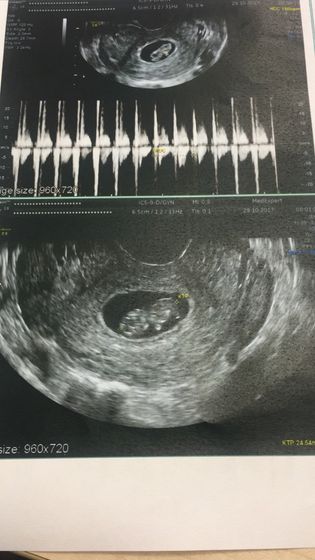

Вот и произошло мое первое знакомство с малышом ?? Такой пузатик )) Ручками и ножками шевелит ☺️ и так сладко бьется сердечко ❤️ Теперь ещё с большим желанием жду встречи ??? На 9 неделе самочувствие приходит в норму и усталость почти уступила ☺️☺️☺️ А как вы ?)))

Спасибо большое ??❤️ А у вас на первом УЗИ тоже был виден такой животик ?))

Я про малыша )) удивилась, что размер животика такой, как голова ?

Не, я в 12 нед ходила голова была уже чуть меньше